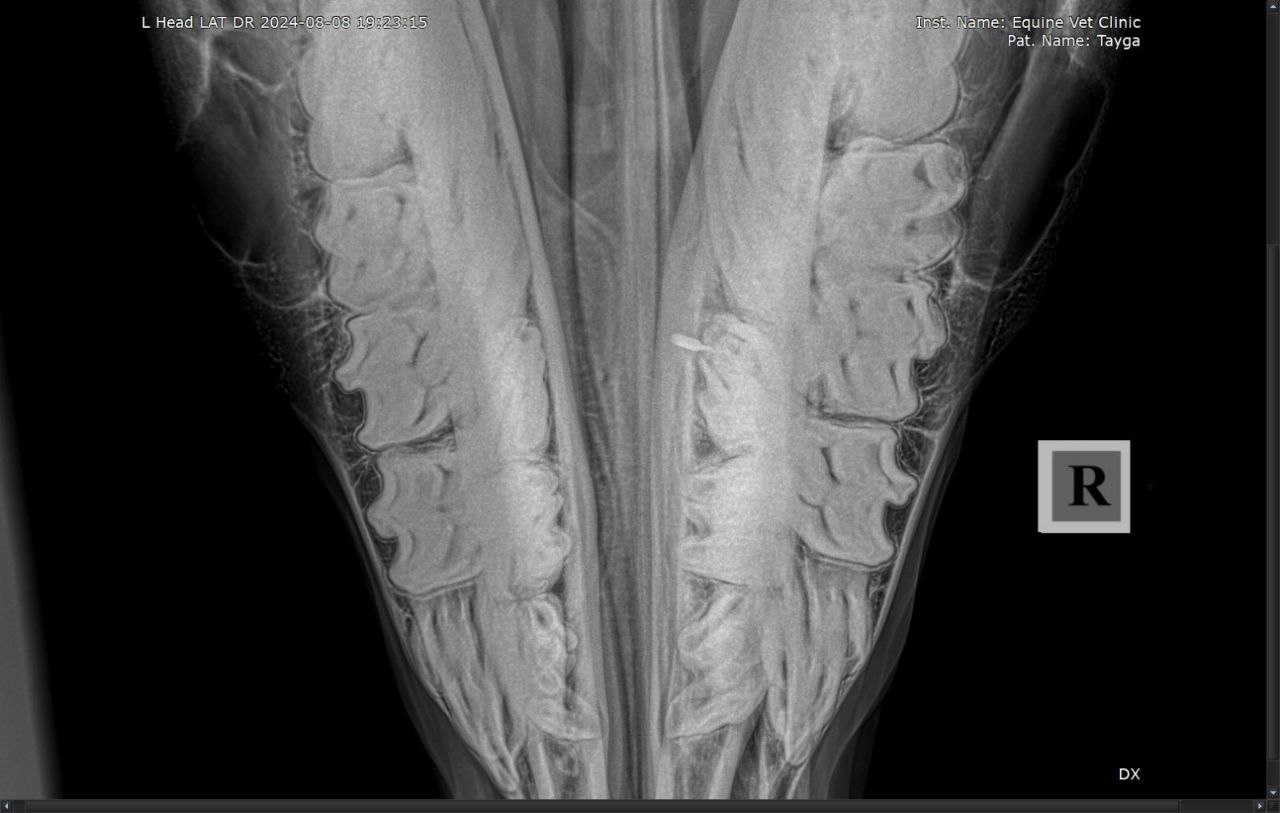

Результаты рентгенологического исследования: наблюдается неравномерная рентгенологическая плотность вокруг верхушки корня и утолщение кортикальной зоны кости нижней челюсти в проекции 408 зуба. Зондированием свища в нижней челюсти установлена вовлеченность корня 408 зуба в формировании канала свища.

Осмотр ротовой полости и зубов: отклонений в целостности и форме 408 зуба не выявлено. Пальпаторно и визуально извне наблюдается утолщение правой ветви нижней челюсти и наличие свища.

Диагноз: апикальный абсцесс 408 зуба с формированием свища нижней челюсти.